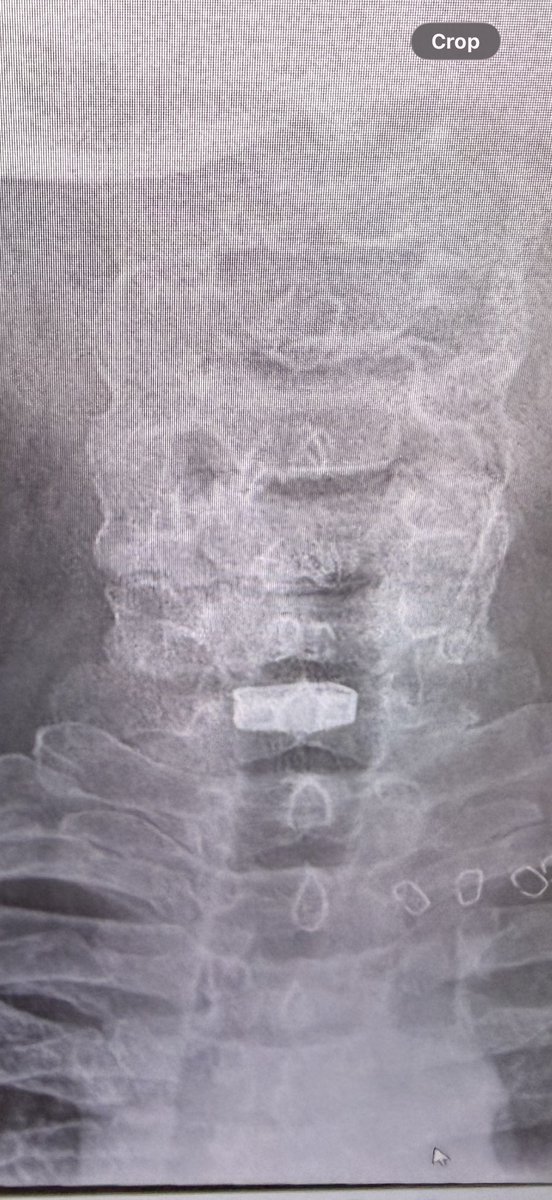

6 weeks today, healing is incredible, tomoz back to driving… physio is hard work! The only issue is the voice very strained by the end of a day (no afternoon meetings 😎) outstanding work by Frimley Park Hospital Another few weeks should be back on the mighty @bmwmotorraduk GSA

Just over a month since the awesome Dr Jandoo & team @FrimleyHealth operated on my spine - the results are incredible and the voice is getting better everyday- looking forward to a full return to my CFAV role @aircadets @ComdtAC @RegComdtLASER